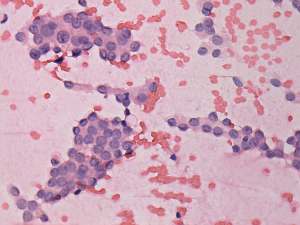

Cytology. Papillary cancer was diagnosed in the nodule in the left lobe and a metastasis of the thyroid cancer into one of the enlarged lymph nodes.